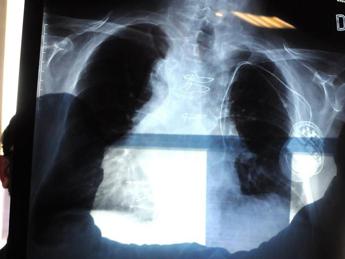

(Adnkronos) – "In Italia l'amianto è presente ancora ovunque e anche in modo insospettabile, senza che nessuno intervenga". Lo denuncia Antonio Giordano, oncologo italiano in forze negli Usa, dove è arrivata forte la testimonianza del giornalista Franco Di Mare che ha rivelato la malattia contratta presumibilmente negli anni trascorsi da inviato di guerra nei Balcani. La sua storia "ha scosso anche l'America. Siamo al suo fianco", dichiara all'Adnkronos Salute lo scienziato, presidente della Sbarro Health Research Organization (Shro) e professione alla Temple University di Philadelphia. Da un lato "urge eliminare definitivamente l'amianto presente nell'ambiente", dall'altro "serve mettere a punto un adeguato sistema di monitoraggio degli ex esposti", esorta Giordano, convinto che invece "interessi economici rallentano la ricerca scientifica". "Il mesotelioma pleurico – spiega l'oncologo – è un killer silente, ma allo stesso tempo è uno dei pochi tumori per cui l'eziologia è pressoché certa: lo sviluppo di questa neoplasia è certamente correlato all'esposizione a fibre di amianto". Giordano lo sa bene, sia perché "studio il mesotelioma da tantissimi anni" sia perché "posso definirmi un 'figlio d'arte'. Mio padre Giovan Giacomo Giordano – racconta – fu uno fra i primi scienziati, insieme al professor Cesare Maltoni del Collegium Ramazzini di Bologna, a studiare e a scoprire i gravissimi danni derivati dall'esposizione alle fibre di amianto e anche grazie alle sue ricerche l'amianto è stato messo fuori legge in Italia nel 1992". Un bando adottato "a livello europeo dal 1999". Eppure di mesotelioma si continua a morire e accade "per due motivi", ragiona lo scienziato. Innanzitutto per la "lunga latenza clinica del tumore, considerando che tra l'esposizione al minerale e lo sviluppo della malattia possono intercorrere fino a 30 anni". E poi perché, "nonostante ogni attività di estrazione, commercio, importazione, esportazione e produzione di amianto, prodotti di amianto o prodotti contenenti amianto sia stata vietata, il materiale è ancora presente in grandi quantità – avverte Giordano – nei luoghi in cui non si è provveduto alla bonifica e allo smaltimento". "L'aria avvelenata, anche dall'amianto, continua a far male" tanto che "ormai il rischio di sviluppare mesotelioma è diventato ambientale – precisa l'oncologo – piuttosto che professionale. Le peculiari caratteristiche fisico-chimiche dell'amianto giustificano il suo vastissimo utilizzo nell'edilizia per cui, se è presente in grandi quantità in zone come l'Italia, si può solo immaginare quante fibre di residui tossici ci possano essere in zone coinvolte da azioni belliche: residui derivanti dalla distruzione di edifici, dalla combustione e dall'ossidazione di inquinanti che restano in sospensione nell'aria, che penetrano nelle falde acquifere e nei terreni coltivati. Scenari che hanno visto coinvolto il giornalista Franco Di Mare". Giordano ha all'attivo diversi lavori focalizzati sul mesotelioma pleurico, "poiché nonostante gli enormi progressi in ambito scientifico – puntualizza – questa neoplasia ancora oggi è orfana di marker diagnostici, prognostici e soprattutto di approcci terapeutici efficaci". Lo scienziato, campano 'doc' nato a Napoli, ha vissuto in prima linea anche la battaglia dei lavoratori dell'ex Isochimica di Avellino: "Una vera bomba ecologica", dice. "Il quartiere di Borgo Ferrovia, nel centro città – ricorda – ha respirato per anni un'aria intossicata dall'amianto. Lo certificano le perizie disposte dalla procura, a cui ho partecipato". "Ad oggi non vi è alcun test che da solo o in combinazione con altri possa essere utilizzato per campagne di prevenzione che possano essere avviate a livello di popolazione", fa notare l'oncologo. Bisognerebbe quindi affinare le armi diagnostiche per poter avviare un monitoraggio sugli ex esposti alle fibre d'amianto. "Invece oggi si assiste a un rallentamento degli studi", che per Giordano "potrebbe essere causato dai forti interessi economici alla base dell'industria dell'amianto". A maggior ragione, dunque, "nelle aree ad alto rischio di patologie asbesto-correlate – insiste lo scienziato – è indispensabile intervenire bonificando nel più breve tempo possibile. Non si può temporeggiare per motivi economici e condannare a morte migliaia di persone". —cronacawebinfo@adnkronos.com (Web Info)